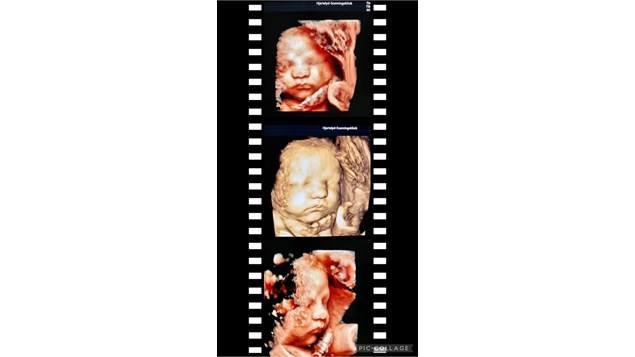

Det kan vi desværre ikke sige - for vigtigst er at baby ligger frit og bevægeligt i fostervandet. Nogle har mere vand end andre. Barnets ansigt kan være gemt bag arme og ben - eller ligge mod mors ryg. Her er det faktisk helt fremme i uge 38. Men da der er godt med fostervand, kan vi alligevel lave fine billeder

Vi anbefaler dog 3D/4D i ugerne 27-34